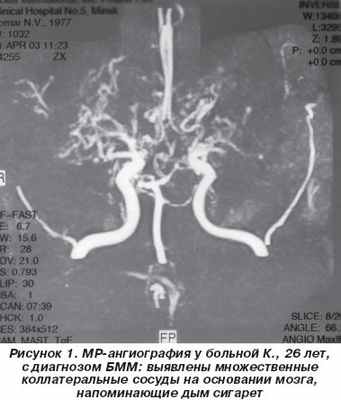

Больная К., 26 лет, домохозяйка, при поступлении в неврологическое отделение жалоб не предъявляла из-за речевых нарушений. Со слов родственников и из анализа медицинской документации выяснено, что в течение последних 3 лет у нее периодически появлялось чувство онемения в правой руке, которому она не придавала значения. Около 6 месяцев спустя постепенно присоединилась неловкость, затем — слабость в правой ноге, стало снижаться зрение. При обследовании по месту жительства при КТ головного мозга обнаружены очаги пониженной плотности в левой теменной области 2,5 см в диаметре, в правой лобной и переднетеменной области — 8 и 9 мм. Лечилась по поводу рассеянного склероза, получала глюкокортикоиды в средней терапевтической дозе с временным улучшением. Спустя месяц остро развилось нарушение речи, лечилась повторно по месту жительства без эффекта, после чего больная была переведена для уточнения диагноза в 5-ю клиническую больницу г. Минска. Из ранее перенесенных заболеваний отмечает редкие простудные заболевания, семейно-наследственный анамнез не отягощен. Замужем, имеет двоих здоровых детей 6 и 4 лет.

Таким образом, у больной с 23-летнего возраста начали повторяться ТИА в каротидных бассейнах, которые закончились формированием множественных инфарктов мозга, что клинически проявилось сенсомоторной афазией и другими нарушениями высших корковых функций (акалькулия, аграфия). Результаты допплерографического исследования и МРТ головного мозга позволили заподозрить сосудистый генез заболевания. МР-ангиография выявила характерный для БММ паттерн — расширение коллатеральных сосудов на основании мозга. Ведущей патогенетической причиной развития болезни в данном случае стал феномен обкрадывания вследствие прогрессирующего тромбоза внутренней сонной артерии и ее ветвей, что подтверждают показатели агрегатограммы. Основной причиной тромбоза артерий, по нашему мнению, стала аутоиммунная коагулопатия, о чем свидетельствовал высокий титр кардиолипиновых антител и антител к волчаночному антикоагулянту. Комплексное лечение (сочетание глюкокортикоидов и непрямых антикоагулянтов) привело к клиническому эффекту.